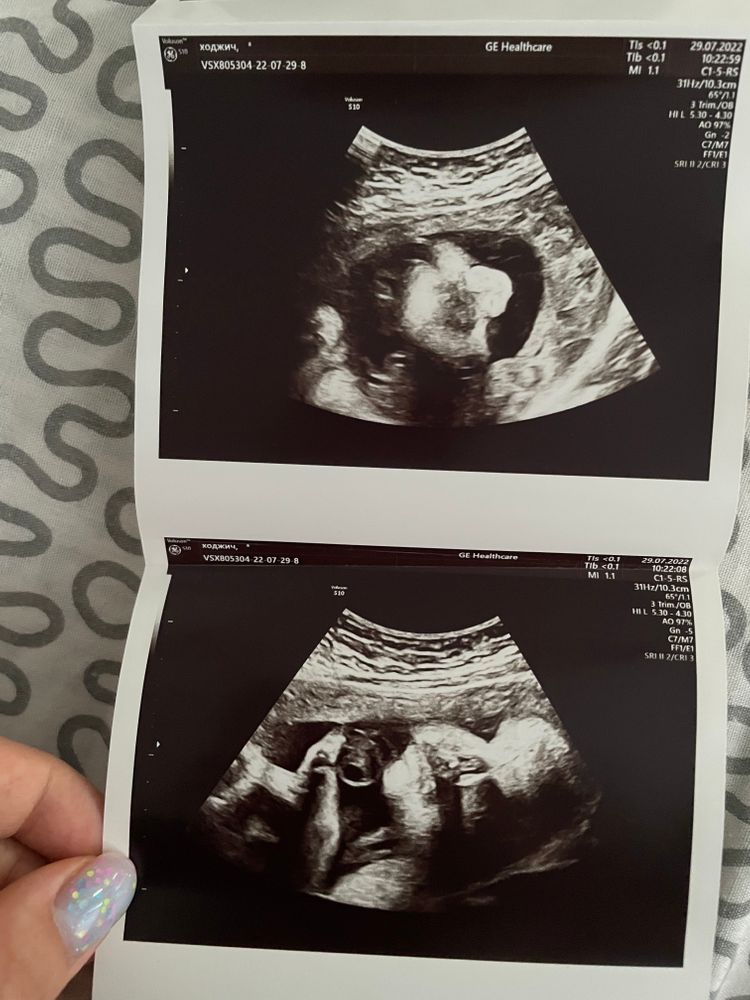

УЗИ, КТГ, доплерДевочки, всем привет 👋. Сделали третье УЗИ на 31 недели, сейчас хотели с мужем в альбом беременности приклеить снимки с УЗИ, но никак не разберем, что и где?!))) Кто разбирается и может помочь, осчастливьте, пожалуйста, нас слепых 😅

4 как будто профиль лица, но такое неудачное

Я вижу только пальчики и личико на 1. А на 4 увидела маскарадную маску😃 и все! Не могу развидеть 😃

А узист затейник) Я и так, и сяк смотрю - что угодно вижу, кроме малыша 🤭